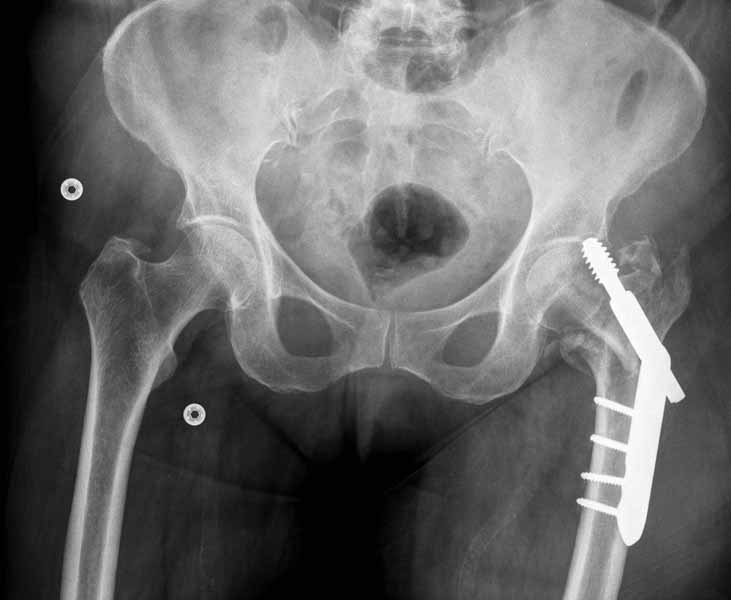

Банальный рутинный перелом чрезвертельной зоны лечимый DHS.

А по картинке можно сказать, что вроде бы все и неплохо. Предупредить миграцию шеечного винта при наружной ротации диафиза во время ходьбы достигают введением последнего поближе к переднему кортексу шейки. На Вашей картинке винт "смотрит" кзади. Отсутствие дополнительной боковой опоры для винта создает предпосылки для несостоятельности фиксации. (См. статью в прикреплении). Поэтому с ранней активизацией пациента в данном случае я бы подождал.

А пациент-то какой из себя?

При таком переломе мы бы тоже поставили вертельный гвоздь - на следующий день встать и побежать - чем не перспектива? На прямом снимке винт стоит замечательно, а коварный аксиальный подкачал, хотелось бы больше по центру шейки и головки завести. Да и смещение, какое-никакое, но есть. Посему - нагрузка 15 кг, а расширяли бы не раньше, чем через 5 недель.

Что касается данного перелома, то по-моему DHS или гамма - принципиальной разницы здесь конкретно нет - медиальная опора сохранена, при правильном исполнении можно ногу нагружать. Технически здесь выполнено на 3+, но если так же винт гаммы поставить - лучше не было бы.

Первые снимки показывают технические погрешности установки DHS. Не была достигнута репозиция, конечность в флексии и шейка в ротации. Сегодня все меньше обращают внимание на параметры для оценки репозиции (S контуры Lowell в обеих проекциях и Garden Alignment Index, в норме 155 и 180 градусов), хотя такие простые тесты помогли бы дорепонировать смещение. Винт находится сзади в головке, что при нагрузке поменяет вектор и вместо компрессии в линии перелома срежет головку-Cut Out!

В зависимости от дистанции линии перелома и латерального кортекса надо использовать разной длины barrel, т.е. конец баррели не должен доходить до пределов перелома. Здесь конец длинного ствола упирается в медиальный фрагмент, что мешает созданию компрессии, а более короткий barrel создал бы запас для компрессии. В боковой пластине вместо 4х можно было ограничится двумя шурупами, потому что головка шурупа в 4.5 мм выдерживает давление до 350 кг.